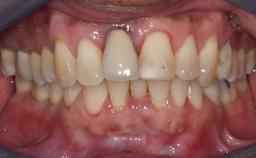

An 80-year-old female patient was referred to clinic for rehabilitation of her dentition. The patient’s medical history revealed no significant findings that would preclude routine dental and oral surgical procedures. She reported no drug allergies and was currently taking no prescription medications.

Her chief complaint was her inability to masticate efficiently due to the recent loss of her mandibular second premolars and first molars bilaterally. She expressed a desire for fixed prostheses in the shortest possible time due to her advanced age, requesting that replacement teeth should look as natural as possible. She was otherwise comfortable and not experiencing any symptoms from her teeth.